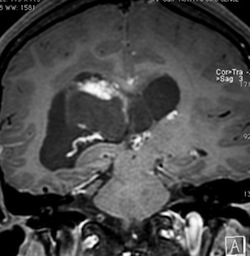

無症状の若い女性に偶然発見された例

central neurocytomaは腫瘍実質部分が多いものです。しかし,この例のように腫瘍の大部分をのう胞が占める症例もあります。

anterior transcallosal apprroachで亜全摘出しました。20代の女性でしたが,その後,子どもも生まれて元気です。

腫瘍の位置から,透明中核が発生母地であることが推測されます。central neurocytomaは,惻脳室壁にべとべとくっつくので,脳質上衣からの剥離は簡単ではありません。鑑別しなければならないのが,成人の毛様細胞性星細胞腫ですが,この症例では決定的な鑑別点はないでしょう。のう胞性の毛様細胞性星細胞腫と同様に,腫瘍の増殖力は低く無理して全摘出するものではありません。